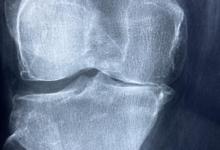

Bildquelle: Praxis integr. Orthopädie Dr. med. Peter Brünings